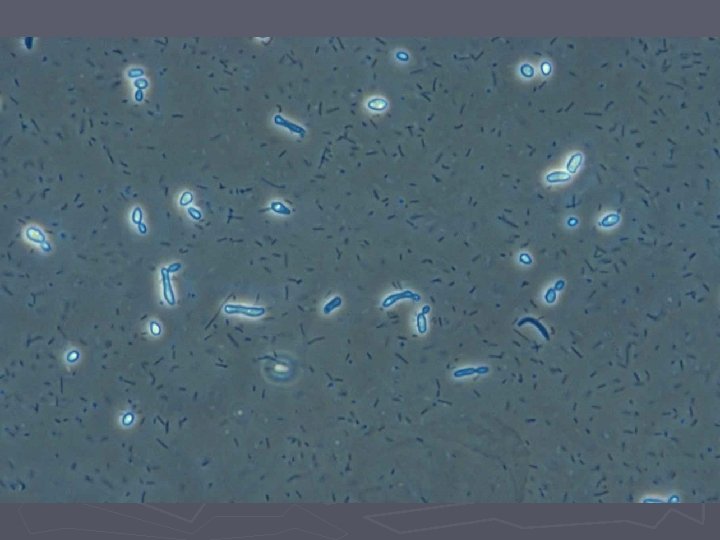

Bakteriel vaginose = BV ► Diagnose (Amsels kriterier) § Tyndtflydende homogen konsistens af flour § Positiv amintest (KOH) § Clue-cells ved mikroskopi § p. H>4, 5 i vaginalsekretet ► 3 ud af 4 kriterier skal være opfyldt

Candida ► Næsthyppigste vaginale infektion ► 80% er Candida albicans ► Asymptomatiske tilfælde ses (vaginose) ► Oftest dog gener med kløe og svie (vaginitis) ► Ved mikroskopi ses sporer og hyfer (KOHpræparatet) ► 10% er Candida glabrata som kun danner sporer.